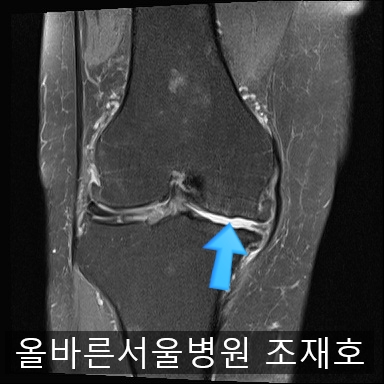

为了掌握具体情况拍了MRI。

image_2475163911519368491057.jpg

内侧关节软骨几乎不见,软骨板也受损严重。软骨损伤部位充满关节液。